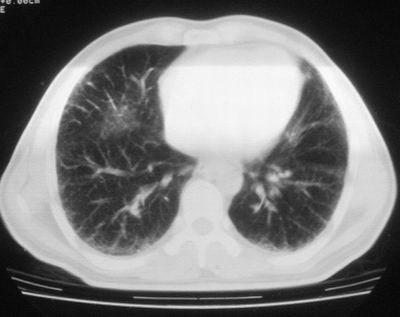

患者,男,44岁,糖尿病4年余,近期消瘦、乏力。化验检查:总胆红素26.33(参考值:5.1-17.2u mol/l),直接胆红素:6.4(参考值:0-4.3u mol/l),谷-丙转氨酶(alt):843(参考值:<40u/l),hbsag(+),抗hbs(-),hbeag(-),抗-hbe(+),抗-hbc(+)。

1\\粟粒性肺结核可能性大,支气管肺泡癌不排除

双肺散在小结节影,考虑粟粒性肺结核.肺窗薄扫会更好看些.

双肺外侧带胸膜下可见网状阴影,考虑轻度肺间质纤维化。

双肺纹理增强并可见网格状影达外带,考虑双肺感染并轻度间质纤维化

1.双肺急性粟粒型肺结核;2.少量腹水.

肺间质纤维化并肺部感染,结合不能排出,毕竟糖尿病人易合并之,建议结合ppd检查或hrct进一步扫描。